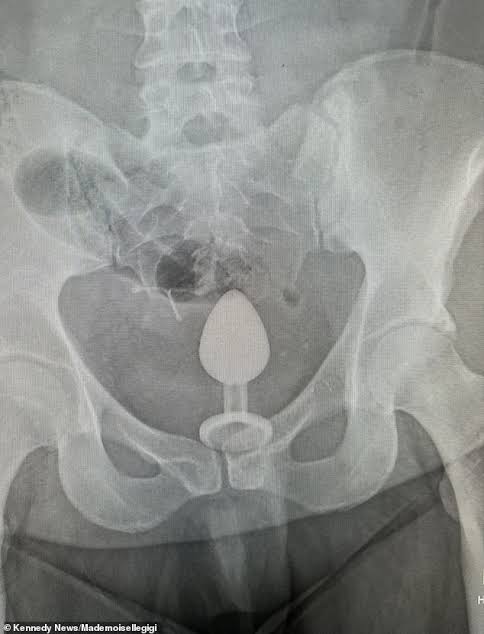

An X-ray revealed the s*x toy was ‘so far up’ even doctors admitted they ‘didn’t know how to get it out’ – and advised Ms Chapman it was safer for her to have it surgically removed.

Ms Chapman told her followers on TikTok of her mortifying trip to A&E and even showed the X-ray in videos which received more than 4,000 likes.